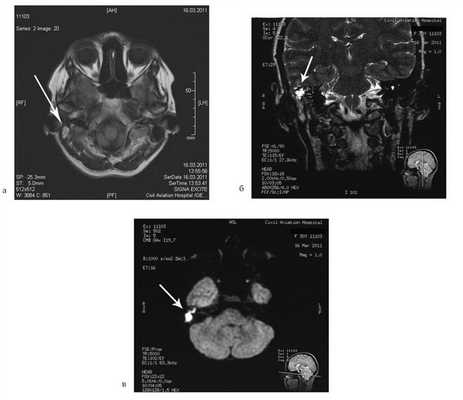

Пациентке была выполнена МРТ основания черепа по описанной методике (рис. 1). Рисунок 1. МРТ основания черепа больной Ф. с хроническим правосторонним гнойным средним отитом. Фистула лабиринта. Холестеатома. а — исследование в режиме Т1; б — в режиме Т2; в — в режиме non-EPI DWI.

В режиме Т1 справа определяется образование с низкой интенсивностью сигнала, а в режиме Т2 и non-EPI DWI — образование с гиперинтенсивным сигналом. Диагноз: хронический правосторонний гнойный средний отит; холестеатома; фистула лабиринта. Пациентка была подвергнута санирующей операции на правом ухе с тимпанопластикой и облитерацией паратимпанальных пространств. Были выявлены холестеатома, заполняющая аттик, адитус, антрум, деструкция цепи слуховых косточек, фистула латерального полукружного канала. Послеоперационный период протекал без особенностей, на 15-е сутки была удалена гемостатическая губка и силиконовая выстилка. При контрольном осмотре ухо сухое, отмечает улучшение слуха, головокружения нет. Через 12 мес проведено повторное МРТ-исследование. Признаков холестеатомы не обнаружено. Получен хороший функциональный результат — ухо толерантно к воде, самоочищается.

![]()

На КТ височных костей справа послеоперационная полость, заполненная мягкотканным образованием, определяется большой костный дефект в направлении сигмовидного синуса и мозжечка (рис. 2, а). Рисунок 2. КТ и МРТ височных костей больной У. с хроническим правосторонним средним отитом. Состояние после радикальной операции (1993 г.), санирующей операции с мастоидопластикой и тимпанопластикой (2003 г.). Холестеатома. Парез лицевого нерва. а — КТ; б — МРТ основания черепа в режиме Т1; в — в режиме Т2; г — в режиме non-EPI DWI.

Больной была выполнена МРТ (рис. 2, б—г).

В режимах Т2 и non-EPI DWI определяется сигнал высокой интенсивности, в режиме Т1 — низкоинтенсивный сигнал. Это может свидетельствовать о наличии холестеатомы мастоидальной полости и пирамиды височной кости. Диагноз: хронический правосторонний средний отит; состояние после радикальной операции в 1993 г. и санирующей операции с мастоидопластикой и тимпанопластикой в 2003 г.; холестеатома; парез лицевого нерва.

На КТ правой височной кости определяется затемнение в области аттика и антрума, цепь слуховых косточек сохранена (рис. 3, а). Рисунок 3. КТ и МРТ височных костей больного А. с адгезивным средним отитом справа, фиброзной облитерацией аттика. а — КТ; б — МРТ основания черепа в режиме Т1; в — в режиме Т2; г — в режиме non-EPI DWI.

Пациенту выполнена МРТ основания черепа по описанной методике (рис. 3, б—г).

В режиме Т1 и Т2 справа определяется очаг с высокой интенсивностью сигнала, тогда как в режиме non-EPI DWI патологических образований не выявлено. Диагноз: адгезивный средний отит справа, фиброзная облитерация аттика.